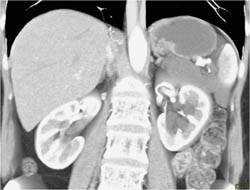

Multiple Intraductal Papillary Mucinous Neoplasms (IPMNs)